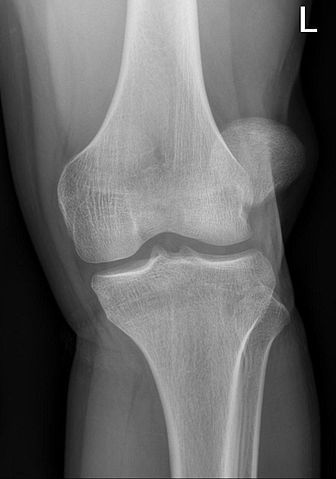

Patellar malalignment is a syndrome or condition that causes pain in the front of the knee or patella (kneecap). The pain commonly affects athletes and active individuals; the pain is associated with activities such as running and skiing. Patellar malalignment is characterized by poor patellofemoral tracking.